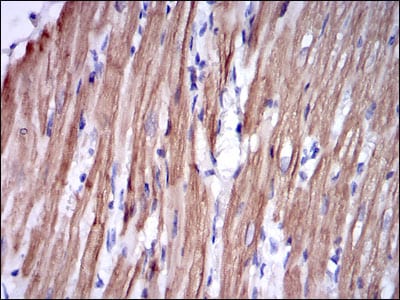

分类: 科研抗体货号: 30259别名: PBT; SCFR; C-Kit; CD117应用: WB,IHC反应种属: Human